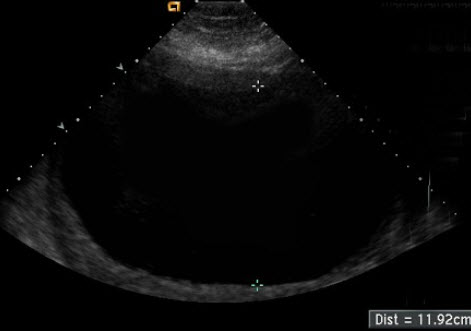

足月妊娠,B超显示如图,考虑_______。

• 足月妊娠,B超显示如图,考虑_______。